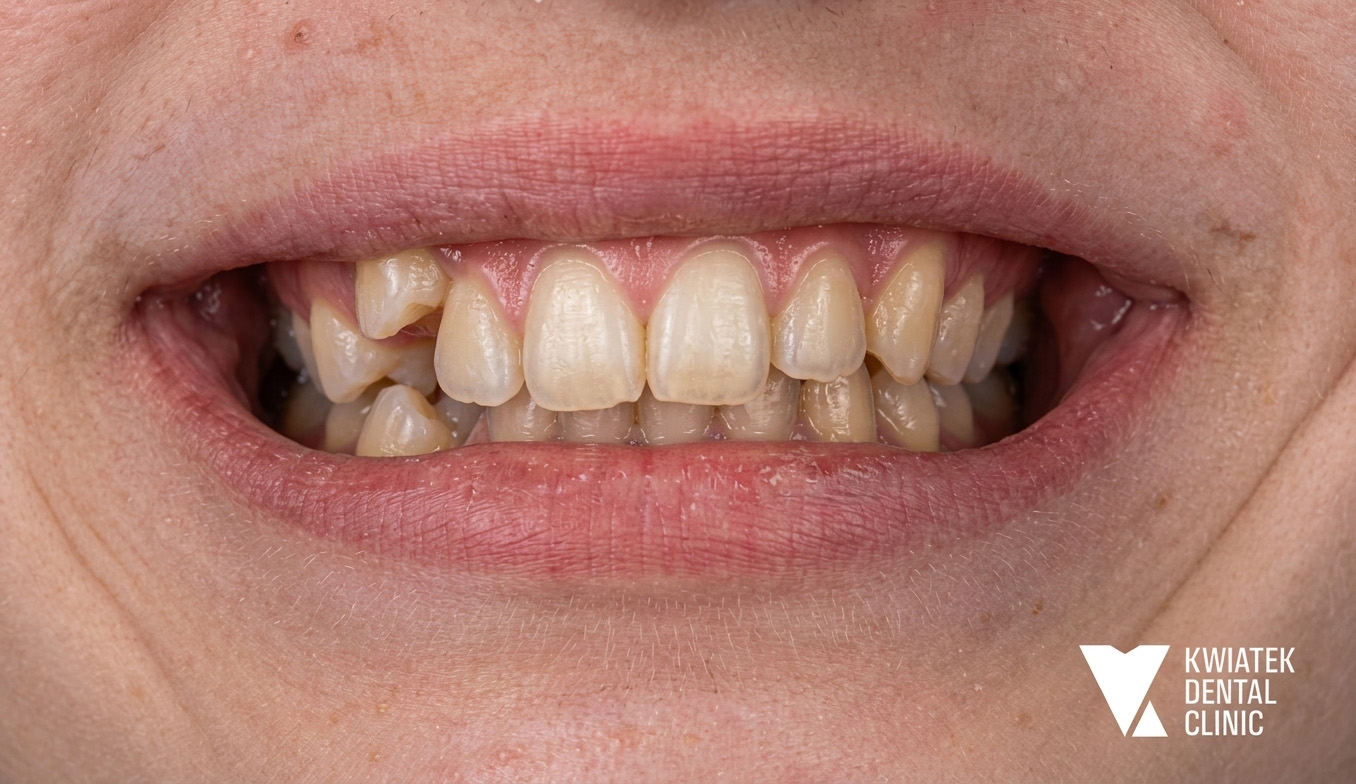

Pełna rekonstrukcja zwarcia i estetyki - historia wymagającej metamorfozy

Pacjent zgłosił się do kliniki z zaawansowanymi problemami stomatologicznymi: licznymi ubytkami próchnicowymi, brakami zębowymi, starciem zębów oraz zaburzeniami zwarcia. Leczenie obejmowało kompleksową diagnostykę, leczenie zachowawcze i endodontyczne, zabiegi chirurgiczne, implantację oraz wieloetapową odbudowę protetyczną. Efektem terapii jest perfekcyjnie zbalansowany zgryz, najwyższy komfort funkcjonowania oraz naturalnie piękny uśmiech, który podkreśla indywidualny charakter pacjenta i pozwala mu w pełni cieszyć się nim każdego dnia.